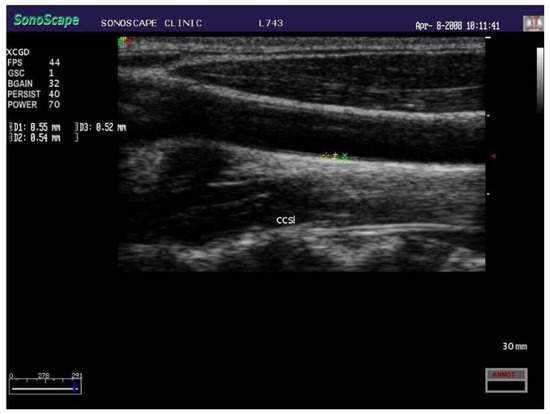

- Dalla Pozza, R.; Ehringer-Schetitska, D.; Fritsch, P.; Jokinen, E.; Petropoulos, A.; Oberhoffer, R.; Association for European Paediatric Cardiology Working Group Cardiovascular Prevention. Intima media thickness measurement in children: A statement from the Association for European Paediatric Cardiology (AEPC) Working Group on Cardiovascular Prevention endorsed by the Association for European Paediatric Cardiology. Atherosclerosis 2015, 238, 380–387. [Google Scholar] [CrossRef]